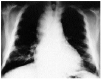

Fig. 1. En la radiografía posteroanterior de tórax se observaba un gran ensanchamiento mediastínico sin datos radiológicos de afectación pulmonar.